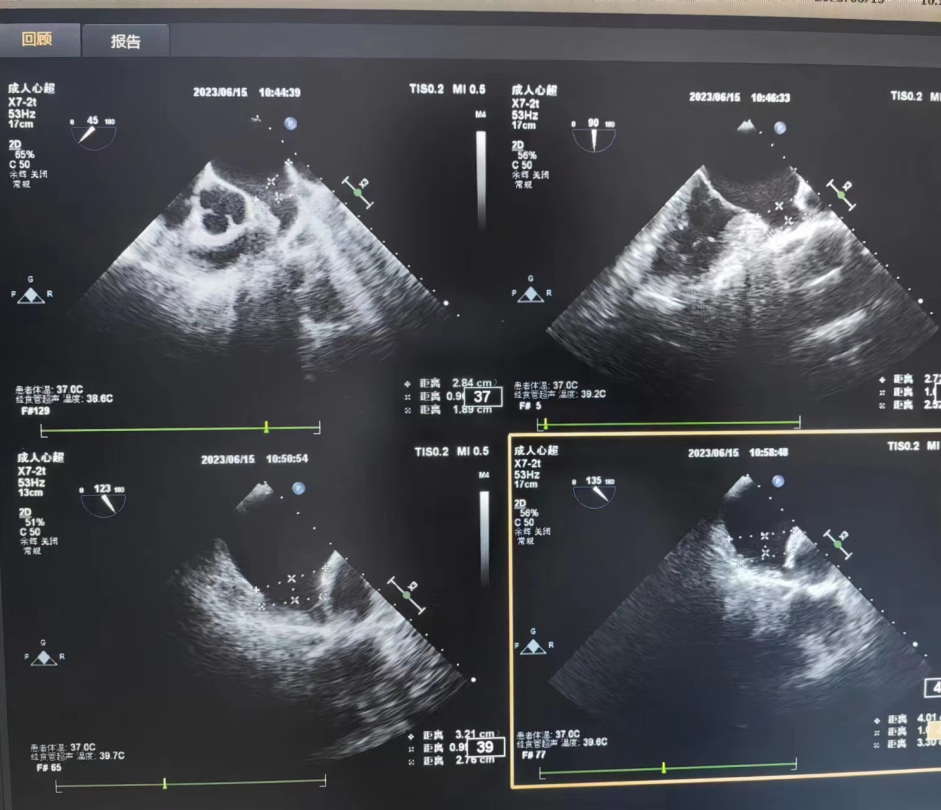

6月15日上午,我院超声科成功开展了首例经食管超声心动图检查(TEE)新技术项目,为患者后续精准治疗提供了重要参考。

经食管超声心动图检查(TEE)是将食道超声探头置于食管或胃底,从心脏后方探查心脏及大血管解剖结构和血流信息的影像诊断技术。近年来,经食管超声心动图检查已经在临床得到广泛应用,对心血管疾病的诊断、治疗以及疗效评价产生了巨大影响,逐渐成为心血管疾病的主要诊疗方法和金标准。

您好!与普通的胸部超声相比,TEE探头直接贴近心脏后方扫查,明显缩短了探头与心脏及其周围大血管的距离,同时也不受肋骨、胸骨、肺及皮下脂肪的干扰,因此图像更清晰,尤其对于心脏后部结构,如对房间隔、主动脉瓣、二尖瓣、左心耳及胸主动脉等结构的显示更具有优势。